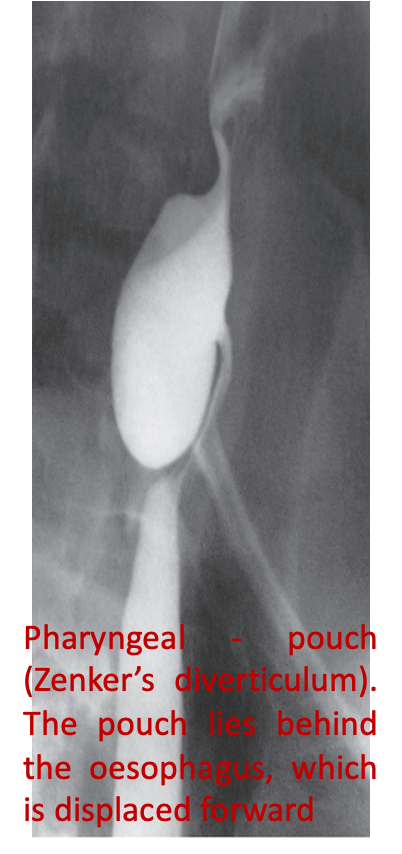

Zenker’s diverticulum or pharyngeal pouch arises through a congenital weakness in the inferior constrictor muscle of the pharynx and comes to lie behind the oesophagus near the midline.

It may give rise to symptoms caused by retention of food and pressure upon the oesophagus and some degree of dysphagia.

Additional symptoms: Regurgitation of undigested food & Halitosis

Barium swallow (best initial test)

Diagnostic finding: a contrast-filled pouch protruding from the esophageal wall